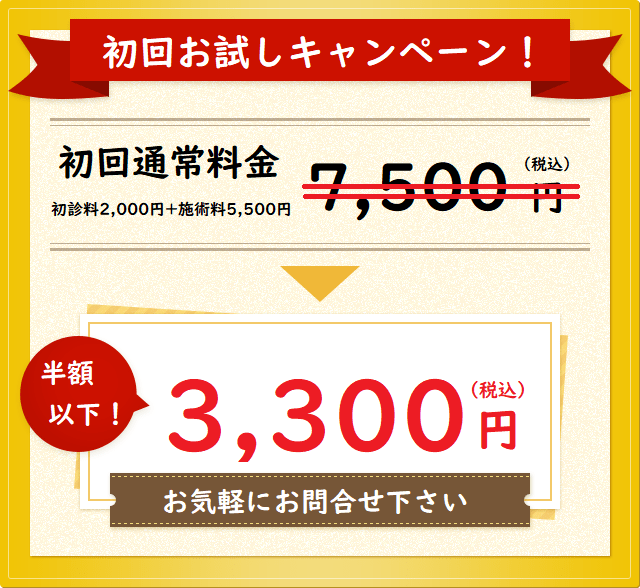

そこで当院が初めての方のために特典をご用意しました。

動悸、めまい、うつ・気分の落ち込み、悲しい気持ち、などが改善した 茅ヶ崎市在住Mさん

当院に来院される前はどのような症状でお悩みでしたか?

心療内科でうつ状態と診断され、リモートワークを経て休職中でした。

気分の落ち込み、動悸、めまい、悲しい気持ち、立ちくらみ、不眠などがあり「死にたい」という言葉も何度も出ており、心療内科で大量の強い薬を出され、心身共に、娘も私(母親)も追い詰められた状況の中で大谷先生と出会いました。

当院の施術を受けてどのようになりましたか?

施術の中で先生がとてもていねいに話を聞いて下さり、頭の中でゴチャついてひどく絡まり合っていたものが、ひといひとつ解けて整理されていくように感じました。

そのひとつひとつに気持ちが楽になるようなアドバイスや新しい視点をもらい、どんどん娘の心が落ち着いてきました。

職場復帰するか退職するかでナーバスになっていたときも、治療・そしていろいろと話を聞いてくださり、前向きに判断する事が出来ました。

最初は週に2回から始め、翌月には週に1回、翌々月には2週に1度でよくなり、今は心身共にとても良好になりました。

治療はもちろんですが、親身に話を聞きアドバイスしてくださることにとても助けられました。

本当に出逢えて良かったです。

ありがとうございました。

※個人の感想であり、効果効能を保証するものではありません。